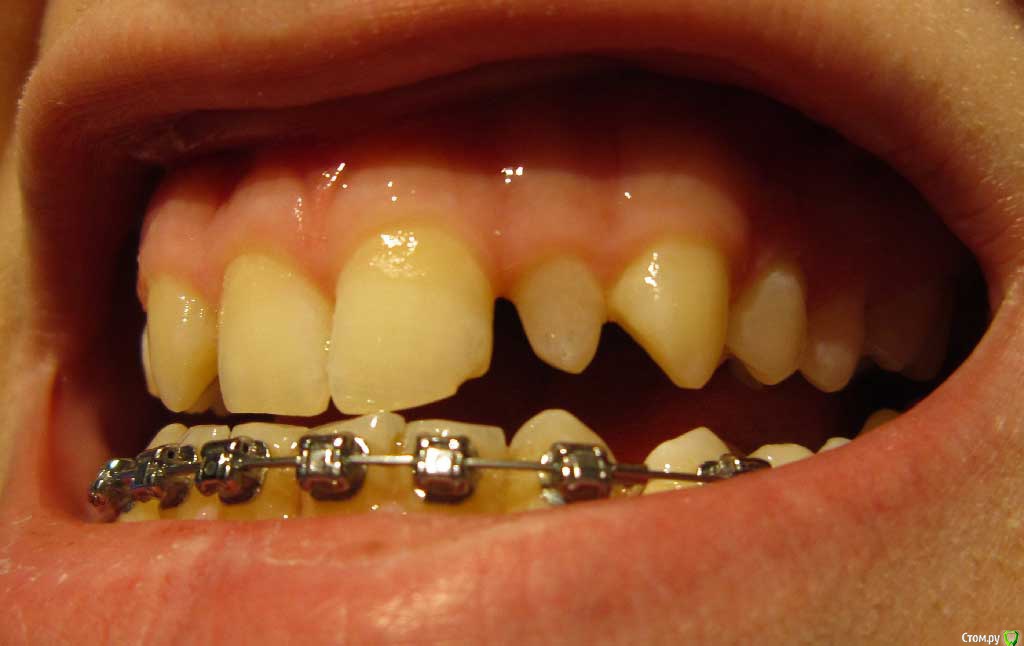

Сейчас мне 17 лет. На лечении у ортодонта с августа 2013 года. Удалили молочные пятерки и стали сдвигать шестерки к передним зубам. На верхнюю челюсть она ставить брекеты не стала. Осенью 14 года врач ушла в декрет.

Пришел новый врач который предложил все сделать несколько иначе: поставить брекеты на обе челюсти, все выравнять и освободить место под будущие импланты: вместо пятерок снизу и второго слева резца сверху -, а пока на их место поставить коронки. Также врач назвал сроки: около 1 года.

Сверху слева отсутствует зачаток второго резца, вместо него находится клык и молочный зуб левее. Внизу нет зачатков пятерок.